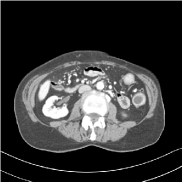

Fig. 2 shows a test example reconstructed using various methods.

Refer to caption

Figure 2: Reconstructions of slice 100 from patient L192 using various methods. The display window is [800 1200] HU.

We observe that PWLS-EP reduces the severe noise and streak artifacts observed in the low-dose FBP images, and the transform learning-based method PWLS-ULTRA further suppresses noise and reconstructs more details of the image such as the zoom-in areas. However, both methods have some blurry artifacts. The standalone FBPConvNet method heavily removes noise and streak artifacts, while introducing several artificial features (e.g., feature indicated by the arrow in the top-right box in Fig. 2). WavResNet denoises the image without introducing artifical features, but still retains some streaks around image boundaries and blurs some details (e.g., feature indicated by the arrow in the bottom-left box in Fig. 2). The state-of-the-art MAP-NN method performs slightly better than WavResNet in terms of suppressing streak artifacts, while it still loses some details as indicated in the zoomed regions. The competing plug-and-play unrolled method—ADMM-Net with WavResNet denoiser—outperforms the standalone WavResNet method, but still has some streak artifacts and blurred details. Compared to these methods, the proposed SUPER methods (SUPER-WRN-EP, SUPER-WRN-ULTRA, SUPER-FCN-EP, and SUPER-FCN-ULTRA) improve the reconstruction quality in terms of removing noise and artifacts, and recovering details more precisely. Two other example comparisons are included in the supplement (Fig. 10 and Fig. 11).